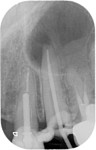

Post removal cases

Premolar retreatment